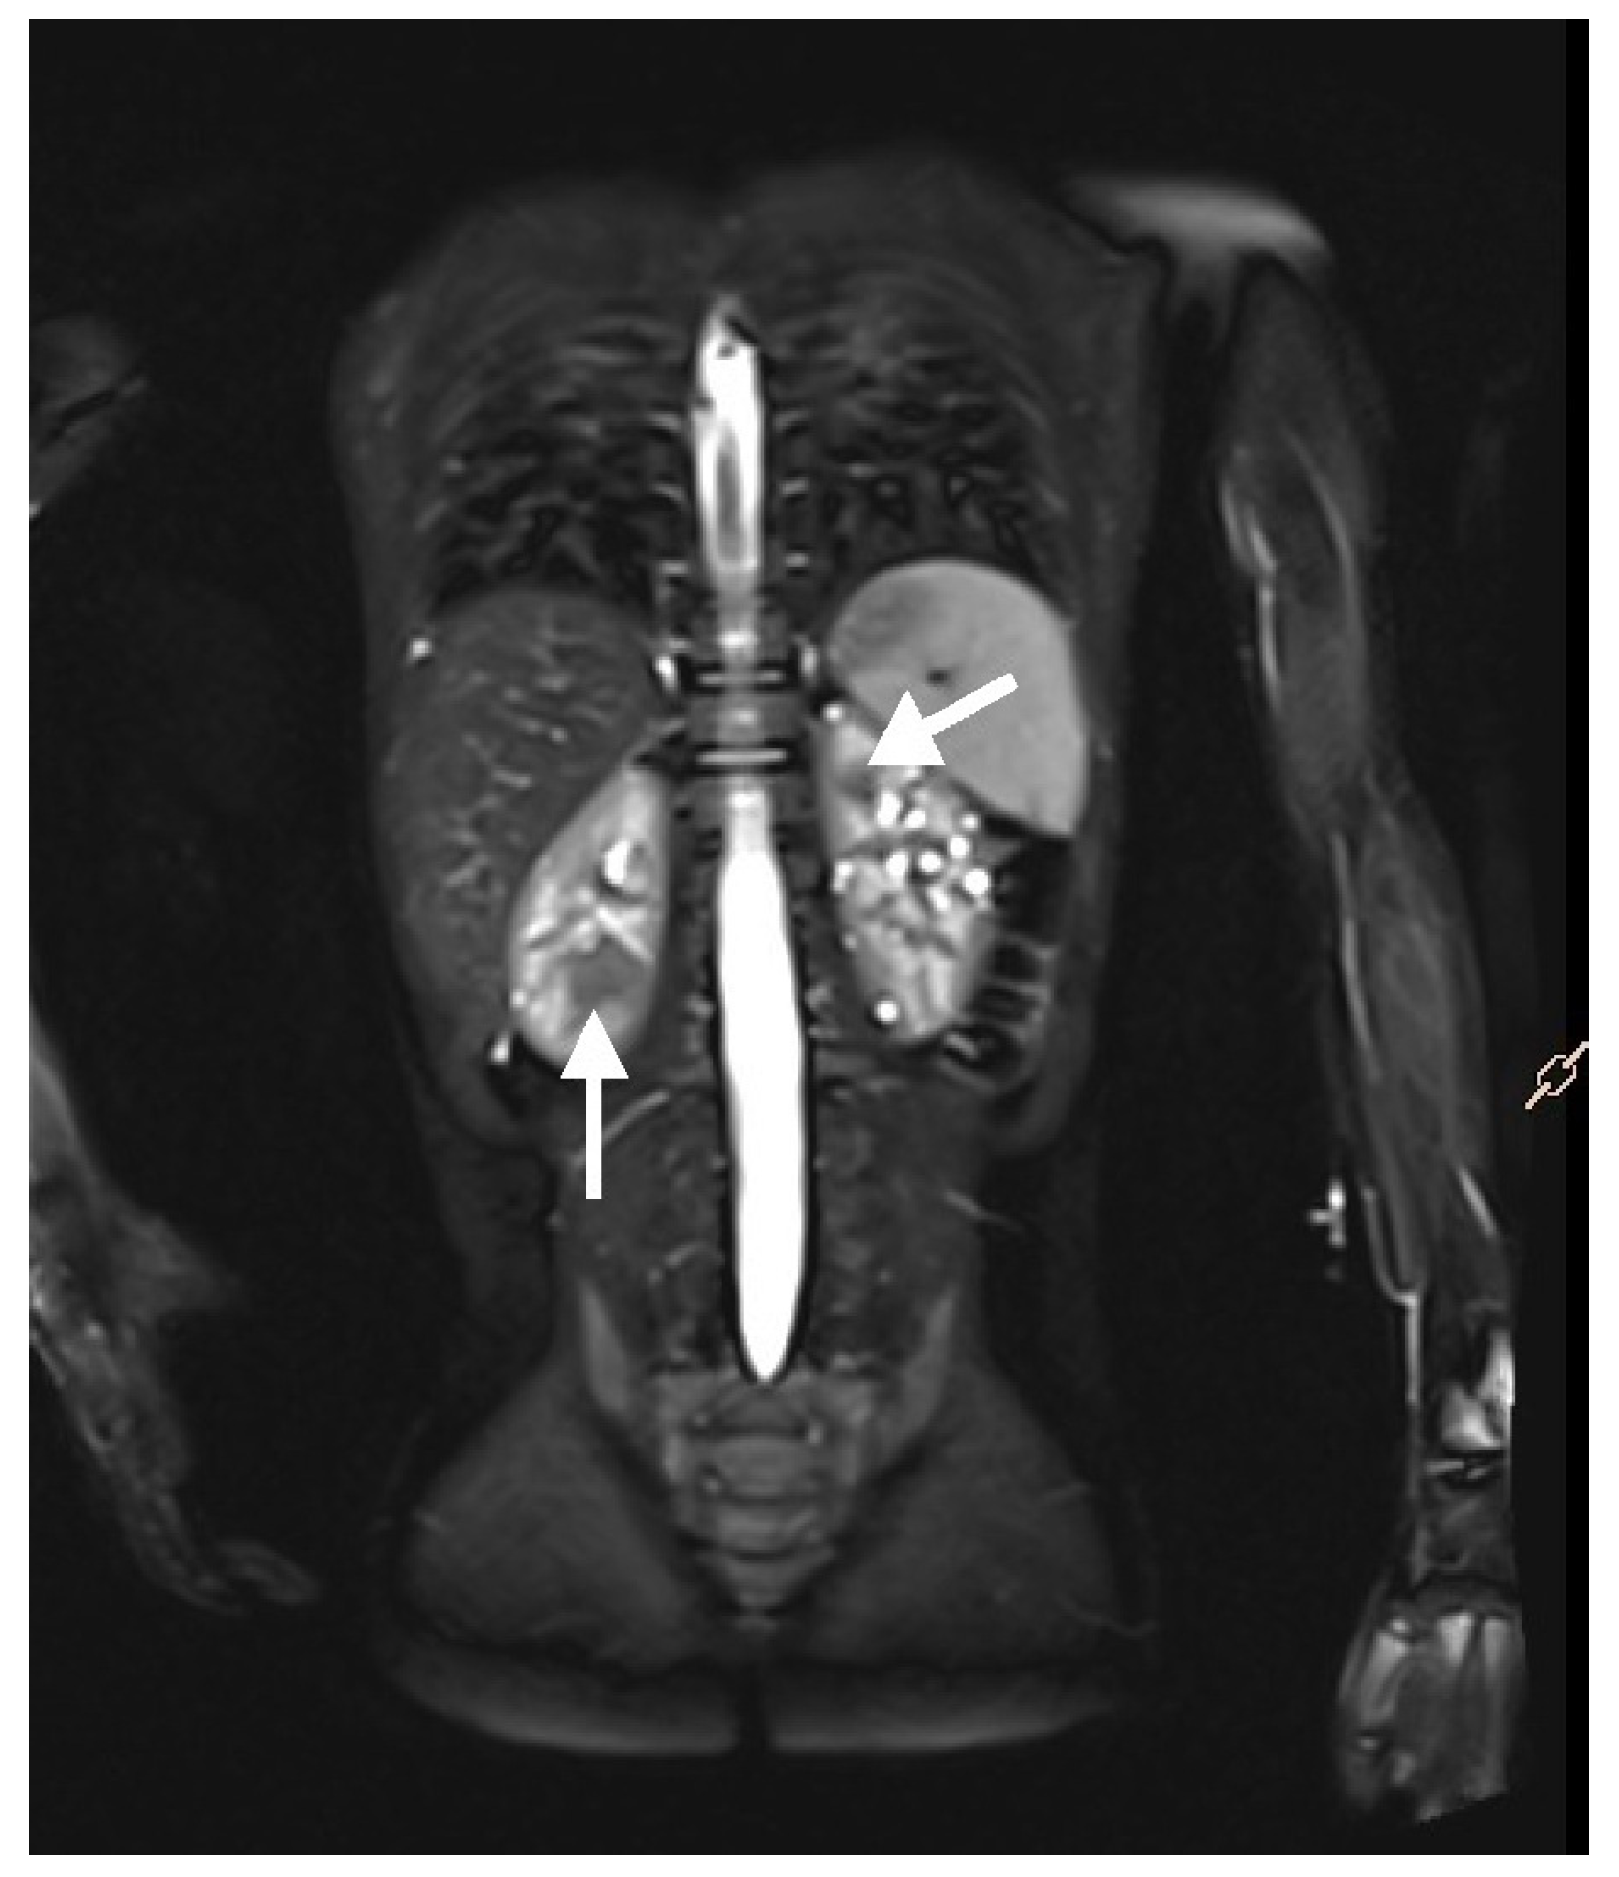

Renal involvement in children with TSC is estimated to occur in approximately 80% of cases. The most common kidney manifestations are angiomyolipomas (70–80%) and cysts (around 50%), presented in Figure 1. Other tumors, including RCC or renal oncocytoma, are less common (<2%) [12,13,14].

Figure 1. Ultrasound (A) and MRI (B) images of a 16-year-old boy. The ultrasound reveals numerous hyperechoic lesions, consistent with AMLs, along with several cysts (A). MRI shows large focal lesions (arrows), most likely representing atypical AMLs (B).